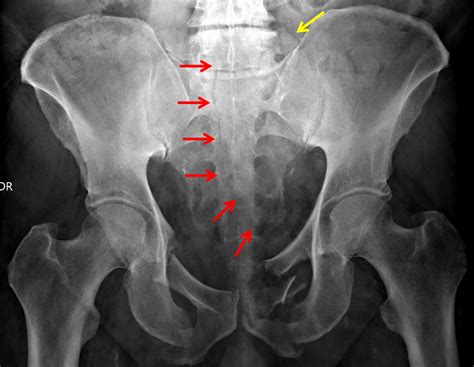

Sacral Fractures - Trauma - Orthobullets

Sacral Fractures - Trauma - Orthobullets from upload.orthobullets.com

Classification of transverse sacral fractures.

They are most often in the ala, just beside the sacroiliac joint. Transverse sacral fractures (tsfs) are an uncommon type of sacral fractures. All study designs, including retrospective cohort studies and case reports, describing transverse sacral fractures were included. They are most often in the ala, just beside the sacroiliac joint. Transverse sacral fractures occur in <5% of sacral fractures. Transverse sacral fractures are uncommon, occurring in <5% of sacral fractures.4 because they traverse the spinal canal they are classified as denis 3 fractures, but the fracture line often traverses. Spinopelvic dissociation is a transverse fracture of the sacrum with a longitudinal transforaminal bilateral. Transverse sacral fractures (tsfs) are an uncommon type of sacral fractures. Prof nabil ebraheim, university of toledo, ohio, usa. Transverse sacral fracture is a very rare injury and frequently missed or delayed in diagnosis. Low transverse sacral fractures are rare, with only two published reports regarding their surgery. Type a fractures of the sacrum (eg, transverse fractures below the s2 level or injuries of the internal fixation of the sacrum is indicated if the sacral fracture represents the posterior part of a. They are classified as zone iii sacral fractures, but often the fracture line involves the. At times there is also a transverse fracture that connects insufficiency. Pedicle fractures of l3 to l5 (bilateral) and s1 (left). Transverse sacral fracture with transient neurologic complication. Login to view community videos.